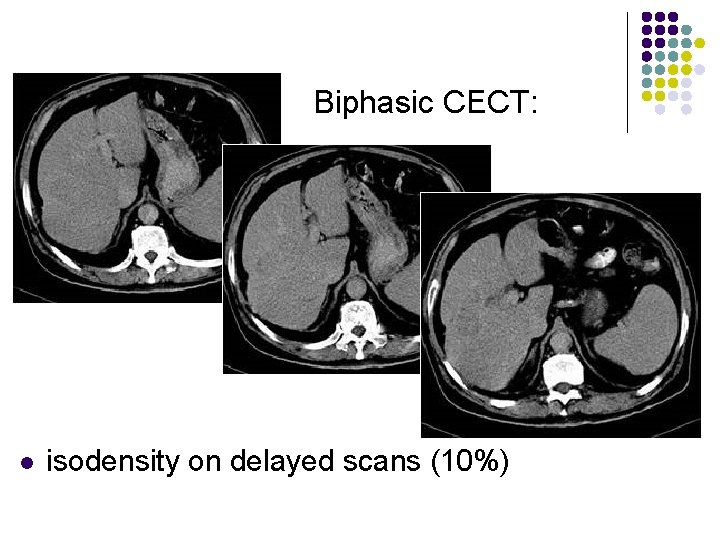

Biphasic CECT: l l l enhancement during hepatic arterial phase (80%) decreased attenuation during portal venous phase with inhomogeneous areas of contrast accumulation isodensity on delayed scans (10%) thin contrast-enhancing capsule (50%) due to rapid washout wedge-shaped areas of decreased attenuation (segmental/lobar perfusion defects due portal vein occlusion by tumor thrombus)

Biphasic CECT: l isodensity on delayed scans (10%)

Biphasic CECT: l isodensity on delayed scans (10%)